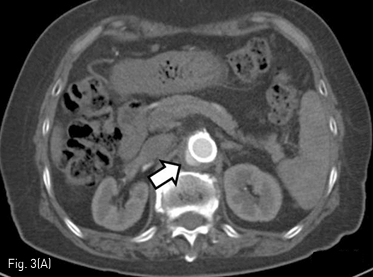

Fig 3A

(A) 3-month follow up CT shows decrease in size of saccular aneurysm (arrow) with eccentric thrombosis at the upper abdominal aorta.

시술 3개월후 시행한 조영증강 CT와 혈관조영 영상에서 복부동맥류의 크기는 0.9 x 1.4 cm으로 줄어들었다. 복강 동맥, 상장간막동맥 그리고 양측 신장동맥의혈류는 잘 유지되어 있었다 (Fig. 3). 시술 6개월 뒤 시행한 조영증강 CT에서는 복부 동맥류의 크기가 더 줄어들어 최대 직경 0.5 cm으로 측정되었다(Fig. 4).